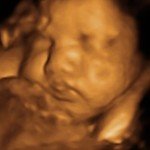

4D/5D/HD Ultrasound Gallery

Gallery